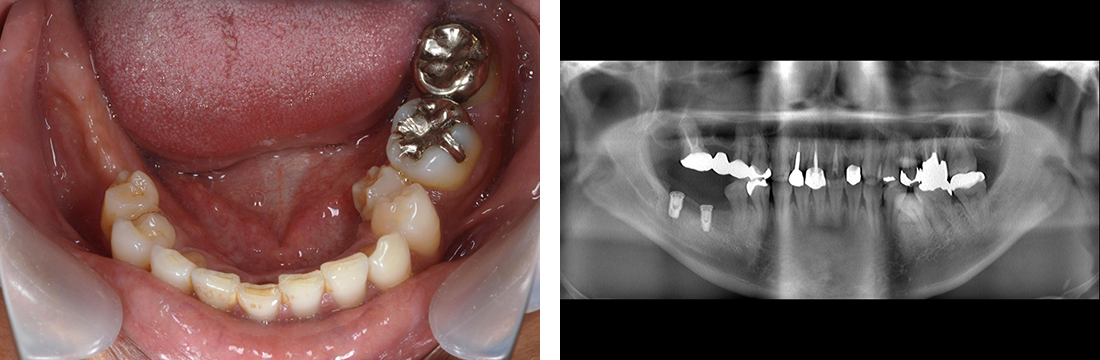

インプラント症例 Case2

Treatment cases

Before

After